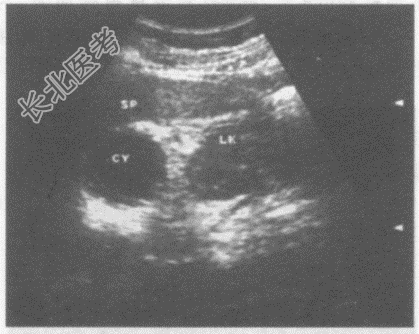

- 单项选择题临床资料:女, 55岁,常规体检。

超声综合描述: 左肾上极与脾之间可见3.4cm×4.0cm圆形无回声区,包膜完整, 后方声加强,CDFI: 内未见动静脉血流信号。

根据超声提示: A、副脾

B、左肾上腺囊肿

C、脾囊肿

D、左肾囊肿

E、脾脓肿

- 该图所显示的病例是(   )